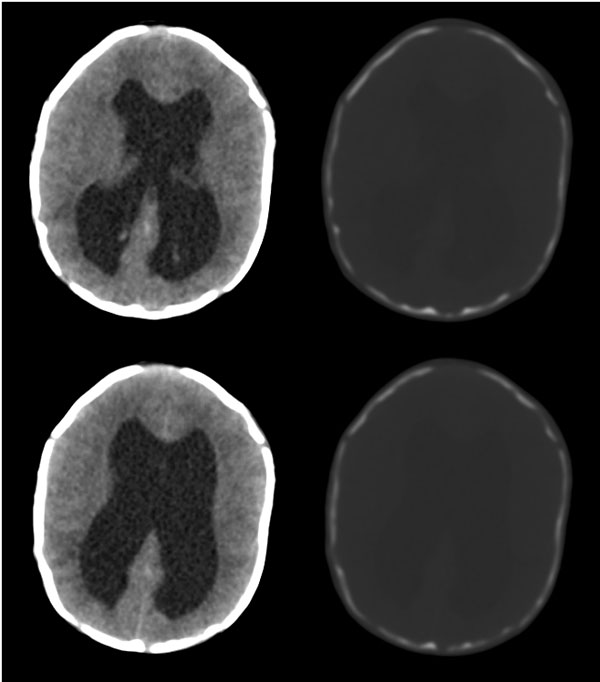

枕骨缺损,脑膜脑膨出。同时第4脑室挤压变形、闭塞,致使第3脑室、双侧侧脑室显著积水、扩张,过高的颅内压推挤脑实质,致使颅骨内板出现多而且深的脑回样压迹,脑细胞水肿,皮质、白质分界不清。

枕骨脑裂畸形伴脑膜脑膨出,双侧脑室扩张积水,第四脑室变窄致使双侧侧脑室及第三脑室积水,

枕骨缺损,脑膜脑膨出。同时第4脑室挤压变形、闭塞,致使第3脑室、双侧侧脑室显著积水、扩张.

脑积水——第4脑室挤压变形、闭塞,致使第3脑室、双侧侧脑室显著积水、扩张

颅骨内面凹陷——过高的颅内压推挤脑实质,过高的颅内压推挤脑实质,致使颅骨内板出现多而且深的脑回样压迹

意见:1,枕骨闭合不全并脑膜脑膨出;

2,第四脑室发育不全或中脑导水管先天狭窄(或闭锁)并幕上脑室扩张积水.

从图像分析看到的是三、侧脑室的积水,颅骨凹凸不平应是脑压高引起的,脑膜膨出是因脑压增大所致。综合考虑是:中脑水管发育畸形(狭窄或闭锁不全)并三、四脑室积水。枕骨发育不全伴脑脊膜膨出。